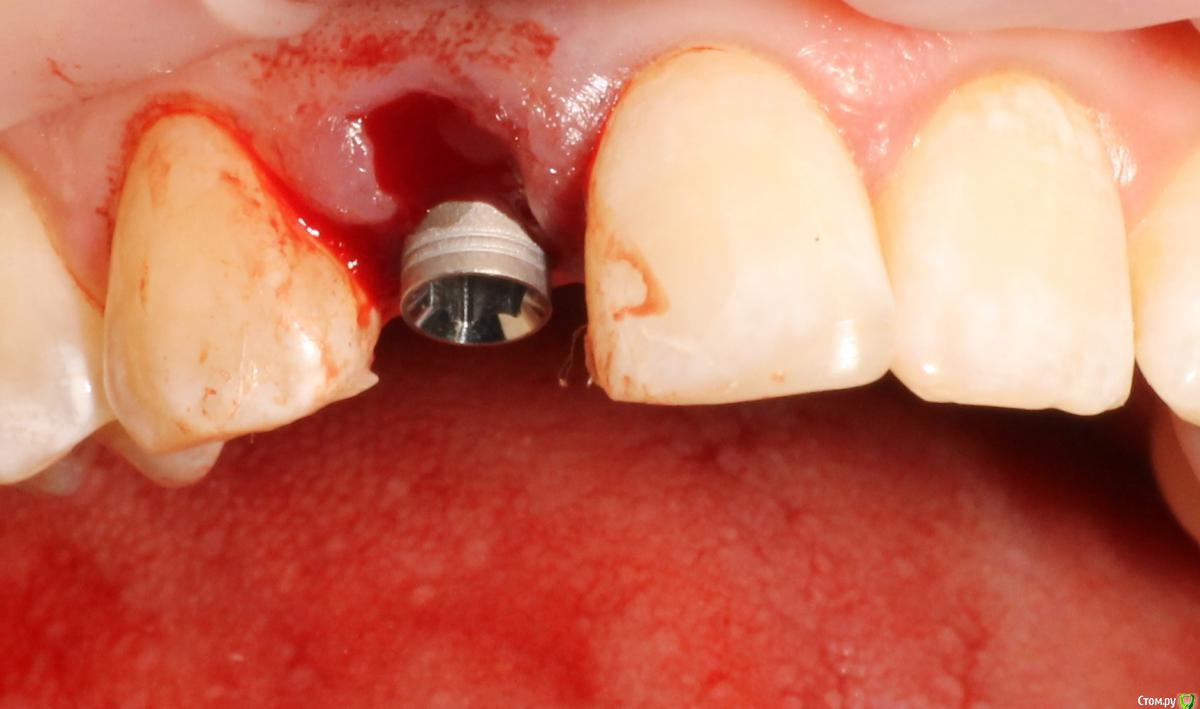

MenshikovDV Опубликовано 2 апреля, 2015 Поделиться Опубликовано 2 апреля, 2015 (изменено) Зуб 1.2 отлом коронковой части зуба, на период ожидания приема у хирурга и ортопеда (2 дня) приклеен к соседям. Вся процедура в одно посещение. Где-то часа два. Я ортопед, хирургия не моя, фото мои Изменено 2 апреля, 2015 пользователем MenshikovDV 19 Ссылка на комментарий

an_ver Опубликовано 2 апреля, 2015 Поделиться Опубликовано 2 апреля, 2015 SPI? В лунку что нибудь кидали во время установки? Ссылка на комментарий

MenshikovDV Опубликовано 2 апреля, 2015 Автор Поделиться Опубликовано 2 апреля, 2015 Нет, ничего не кидали. Ссылка на комментарий

Lolopop Опубликовано 3 апреля, 2015 Поделиться Опубликовано 3 апреля, 2015 альфабио?)))какой торк получили? Ссылка на комментарий

АнтонТЛТ Опубликовано 4 апреля, 2015 Поделиться Опубликовано 4 апреля, 2015 Судя по фото Alpha bio SPI, торк около 40 Ссылка на комментарий

MenshikovDV Опубликовано 5 апреля, 2015 Автор Поделиться Опубликовано 5 апреля, 2015 торк намного больше 40 Ссылка на комментарий